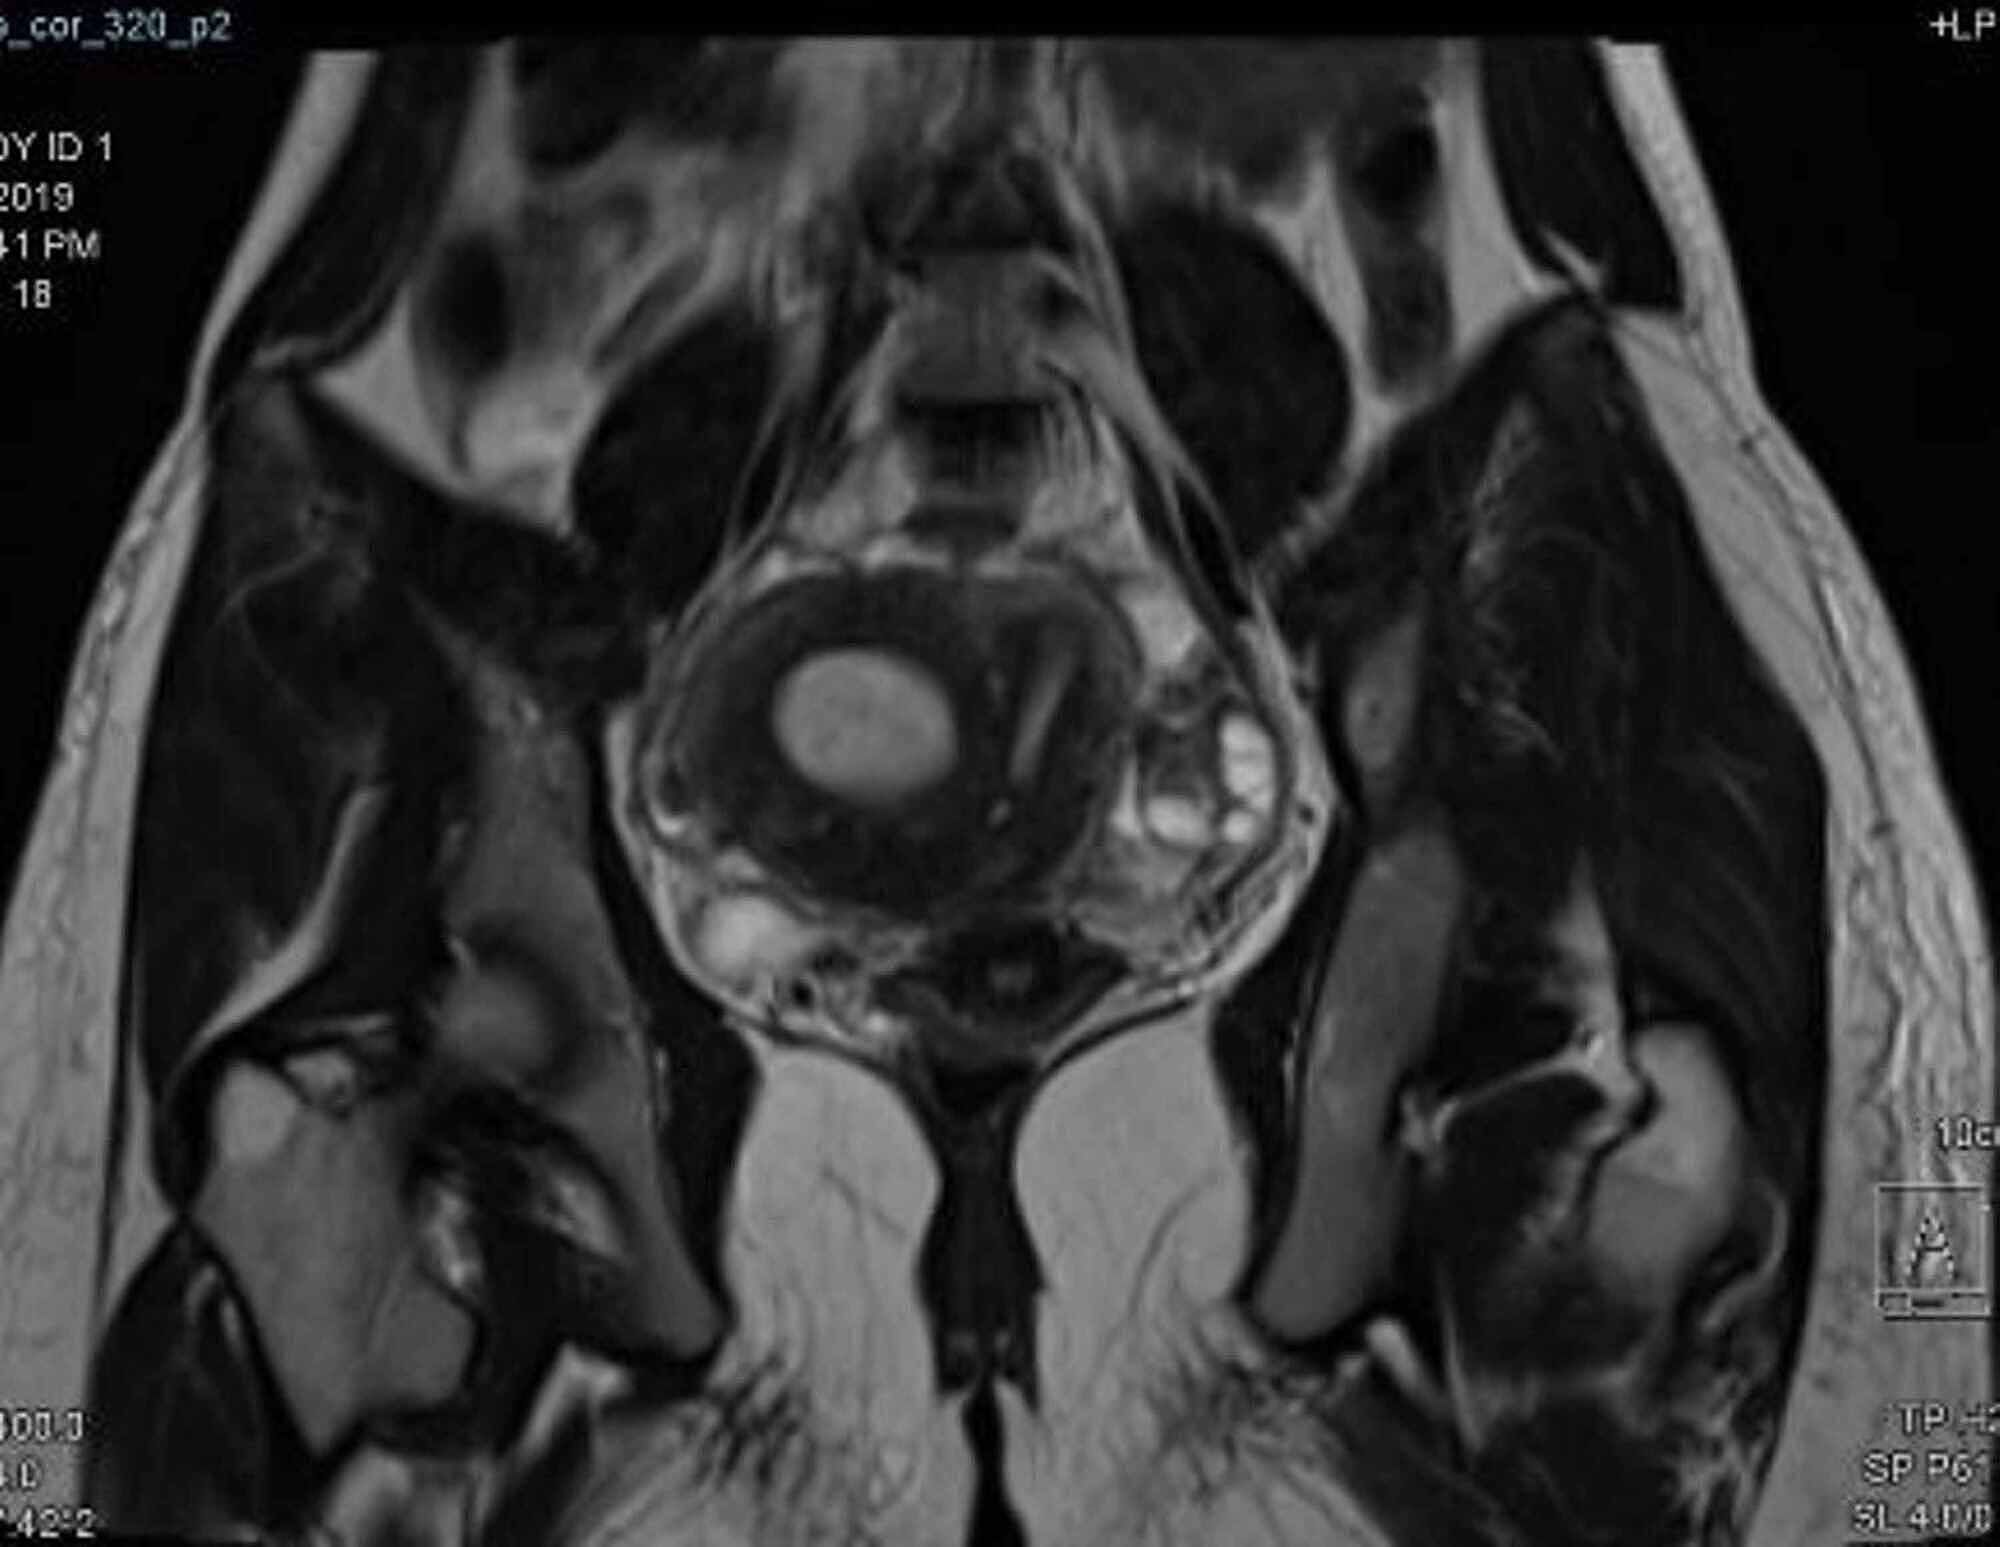

from radiologykey.com

Congenital Uterine Anomalies Radiology Key

Congenital Uterine Anomalies Radiology Key What Is A Rudimentary Horn Of The Uterus the horn is connected to the unicornuate side by either a minimally connected narrow fibrous band of tissue or a broad, firm muscular. the horn is connected to the unicornuate side by either a minimally connected narrow fibrous band of tissue or. a rudimentary horn is what’s left of the uterine tissue that was absorbed. The rudimentary. What Is A Rudimentary Horn Of The Uterus.